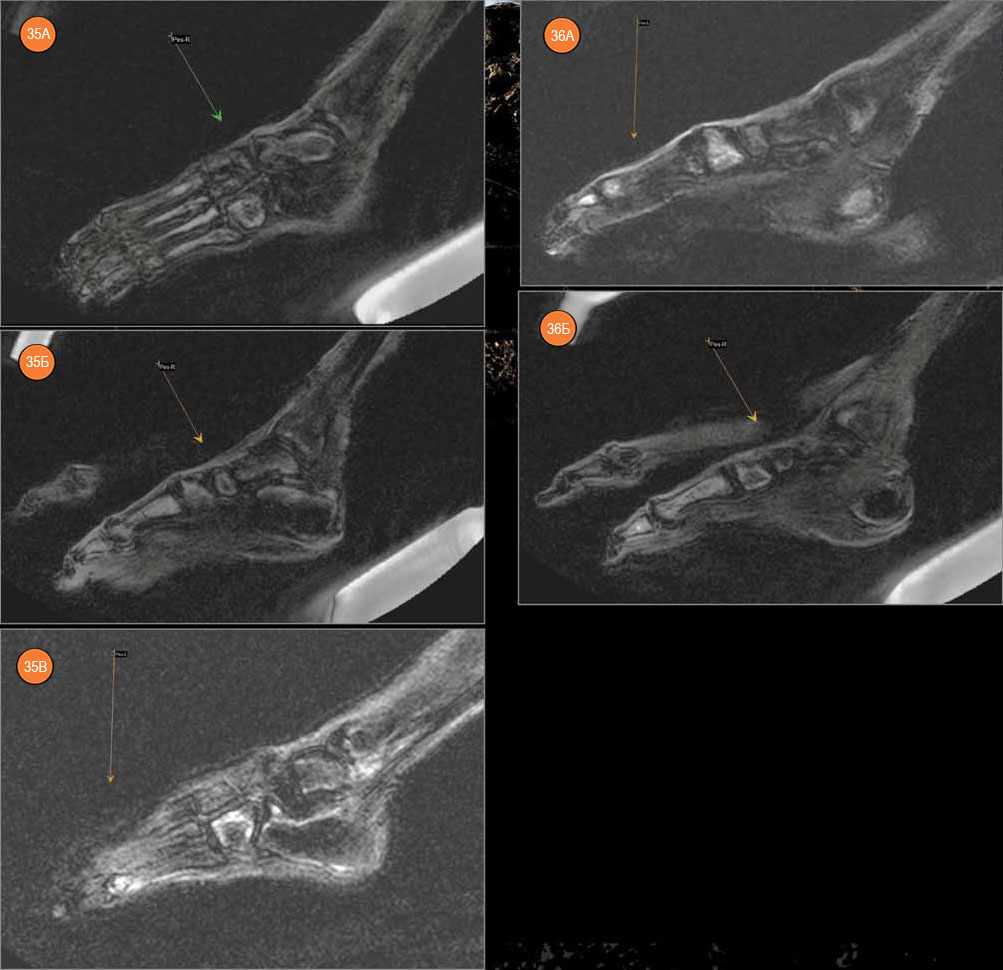

В костях левой стопы выявлены очаги с отечной периферией и с МР-плотными темными центральными зонами. Эти изменения можно интерпретировать как проявления прижизненного инфекционного или, что более вероятно, метастатического процесса. Аналогичные, но менее интенсивные очаги выявлены в костях правой стопы.

Рис. 35. Левая стопа. А — очаг в кубовидной, таранной кости, в плюсневых костях. Б — очаги в кубовидной, пяточной кости и в латеральной лодыжке, в V плюсневой кости. В — очаги в кубовидной, пяточной кости, в I плюсневой кости, в проксимальной фаланге I пальца и в дистальном диафизе большеберцовой кости. Рис. 36. Правая стопа. А — очаги в I плюсневой кости и в проксимальной фаланге I пальца. Б — очаг в правой кубовидной кости